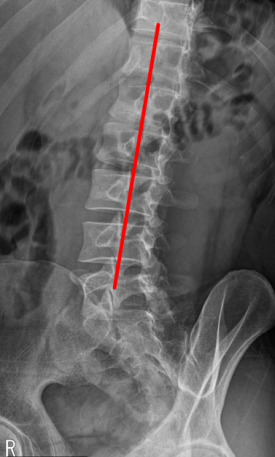

경추 X-ray

SLAP 파열 & 일자허리

일자목 & 디스크 팽륜